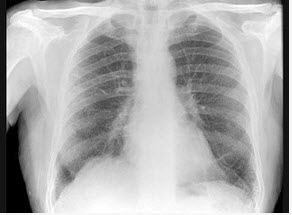

213、单项选择题

男,5岁,临床考虑先心病室间隔缺损,结合图像,下列描述正确的是()

A.肺淤血

B.正常肺

C.肺泡性肺水肿

D.间质性肺水肿

E.肺充血

点击查看答案